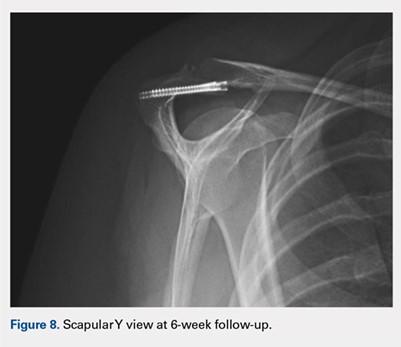

At her second visit (6 weeks), she was completely pain free. Clinical examination showed no tenderness at the acromion, healed incisions, and pain-free passive ROM. Radiographs demonstrated early evidence of consolidation and no sign of fixation failure (Figures 6-8). Her Single Assessment Numeric Evaluation (SANE) score was 85%, and her Simple Shoulder Test (SST) score was 3/12. She was permitted to discontinue the sling, to begin using the arm actively at the side, and progress with unloaded use above shoulder height over the next 6 weeks.